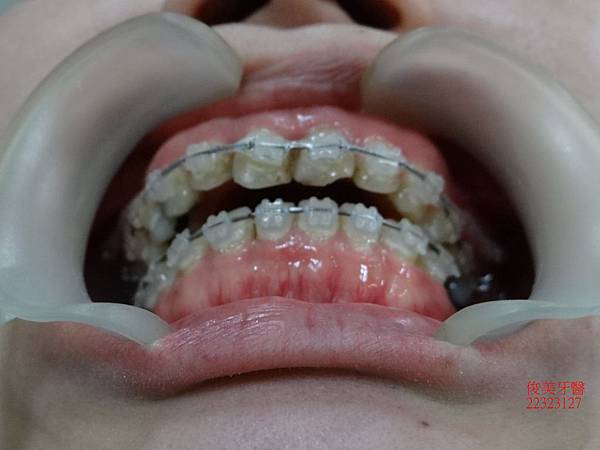

治療中~~~~

將牙齒牙根移到正確的位置。

沒有重疊的現象。

在植牙骨整合完成時即將左下智齒拔除。